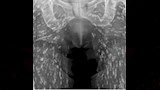

وأثناء الفحص، أجرى الطبيب أشعة سينية كشفت عن وجود مئات الأكياس الطفيلية لمخلوقات غريبة داخل جسم الرجل، نتيجة تناوله لحمًا غير مطهو جيدًا، حسبما ذكرت "ديلي ميل".

ونشر الدكتور سام غالي، طبيب الرعاية العاجلة في فلوريدا، صورة الأشعة على وسائل التواصل الاجتماعي، واصفًا الحالة بأنها واحدة من "أغرب الحالات" التي شاهدها.

وأوضح "غالي" أن البيض الطفيلي الذي دخل جسم المريض عبر اللحم الملوث تحول إلى يرقات شكلت أكياسًا منتشرة في الأنسجة الرخوة بجسمه، خاصة الوركين والساقين.